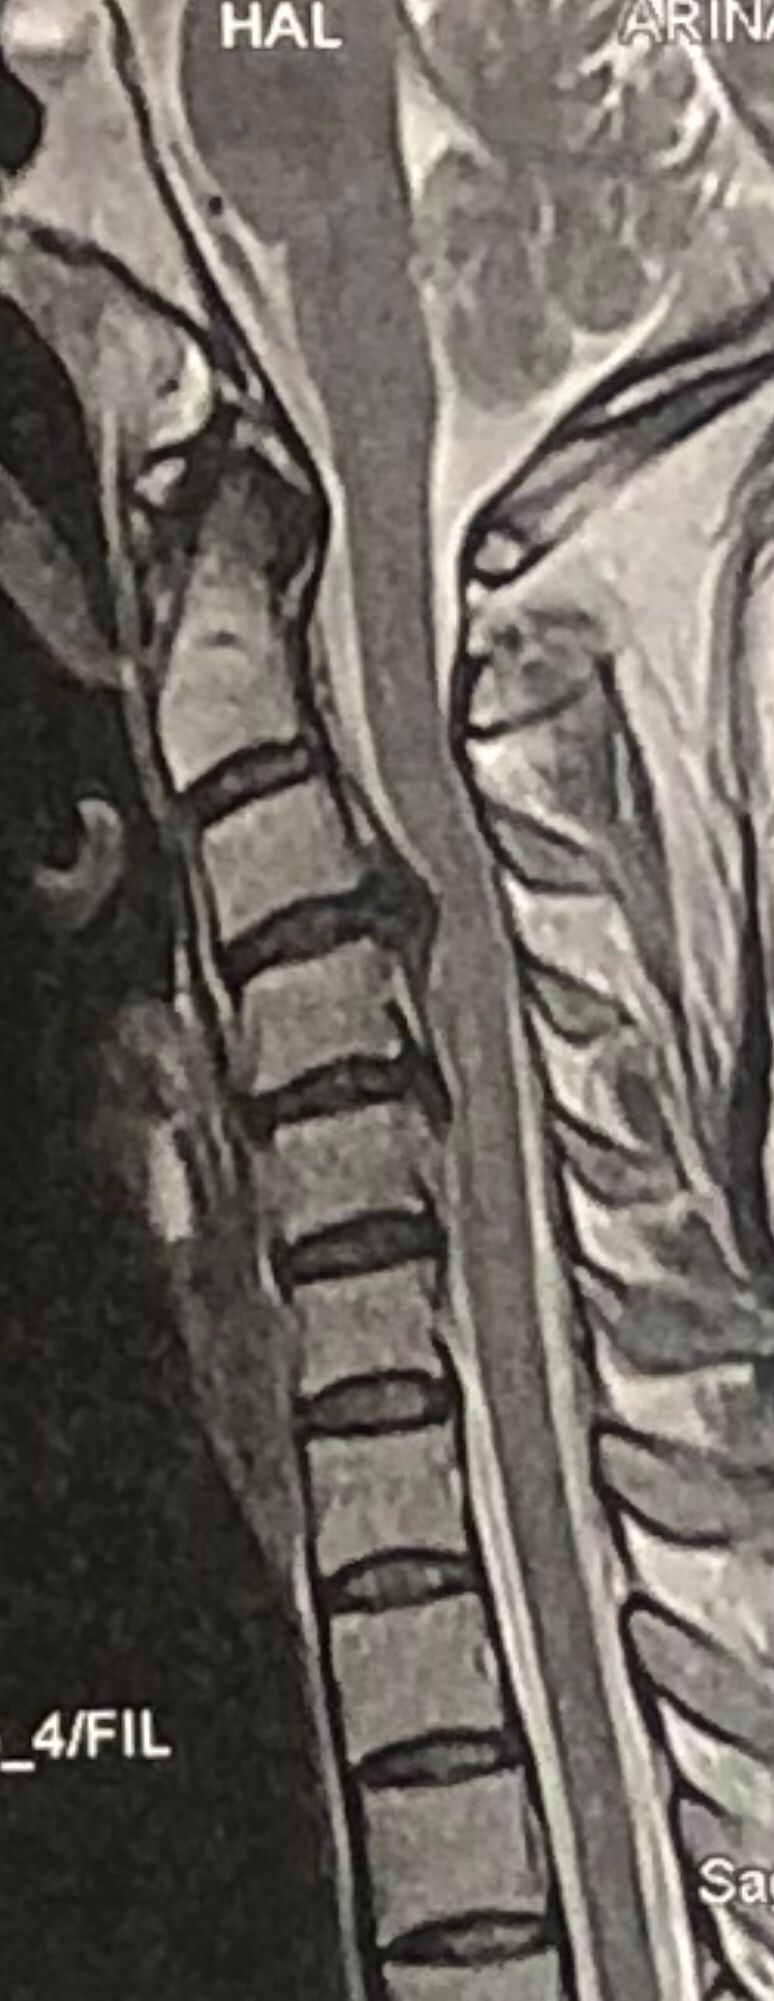

41 years old man presented to my clinic in October 2023 with acute and sever R neck pain with radicular pain to his R upper extremity along C6 dematom since 2 weeks ago. Examination didn’t show any upper motor signs. Was suggested urgent surgery

I ordered EMG/ NCV : showed mild R C6, C7 irritation without any active axonal loss

In his MRI was reported R. para R. IVF Massive extrusion. I decided to control his pain and manage this patient with reevaluation of patient every other session. For 5 sessions i just used acupuncture and laser and IFC and mild adjustments to his R. T3-T7 and mild arthosteem to above and below involved segment. Cervical adjustment considered contraindicated for this patient. From session 6th- 8th i started to use mild/gentle cervical decompression. He used soft cervical collar all the time. His pain decreased by 80 percent

I gave him cervical traction pump to be used 3-5 times per day at home for the next 3 months and i released the patient. He was evaluated every week once for one month and after that every 2 weeks. After 3 month I repeated MRI. Size of the herniated disc was reduced greater than 50 percent. Asked him to do another mri in 6 months

MRIs before and after proper management of this patient: